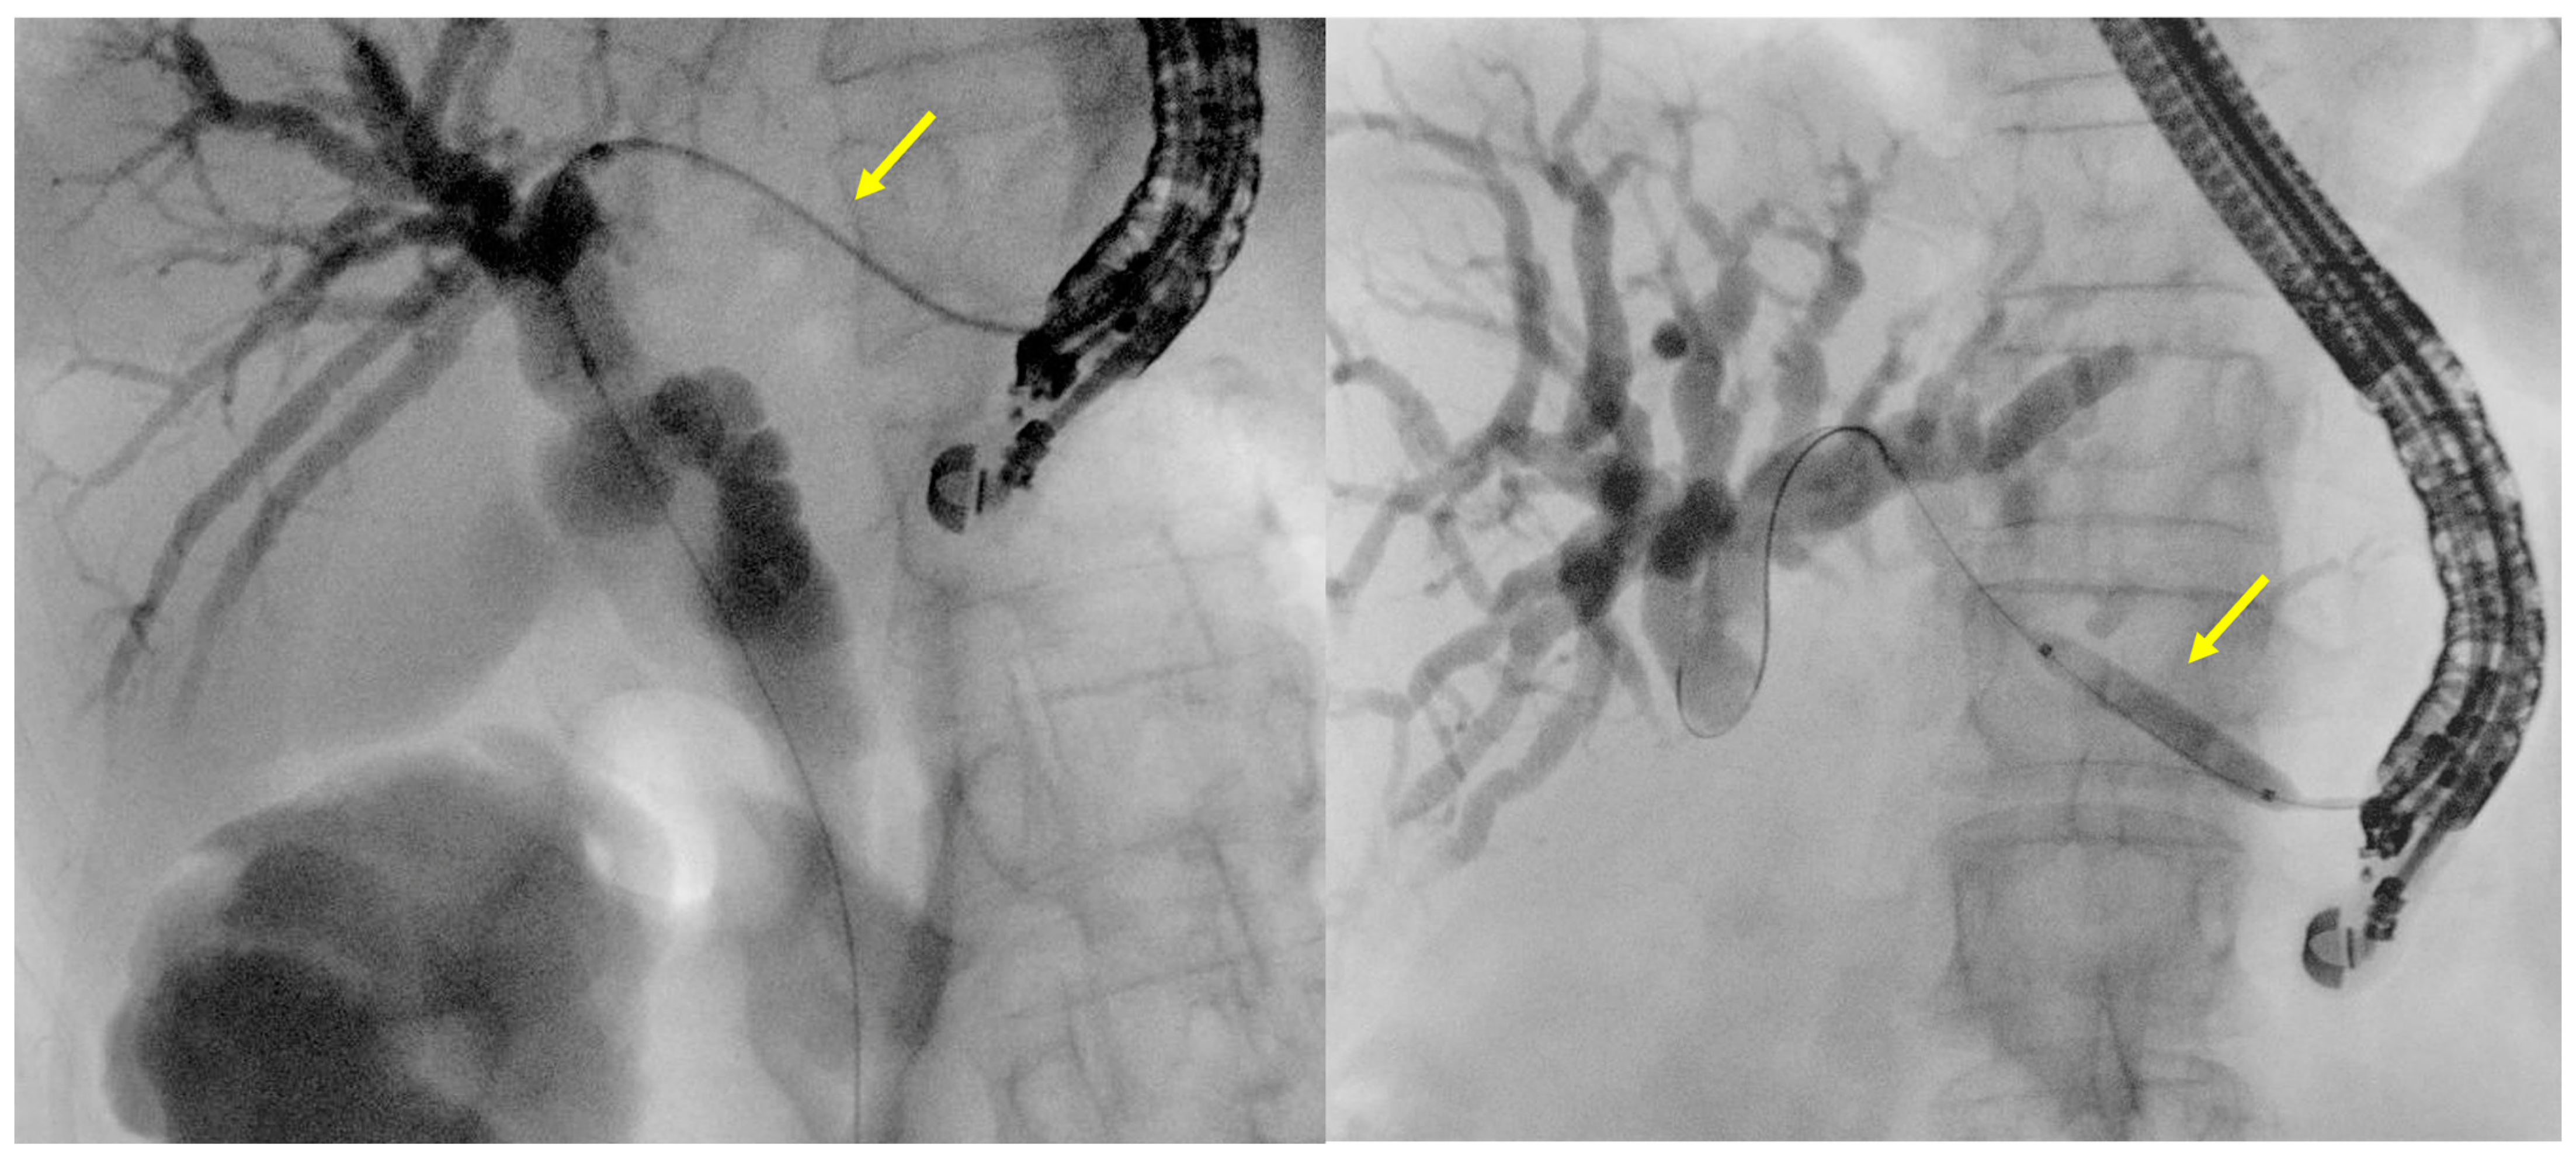

- Tract dilation

- Stent positioning